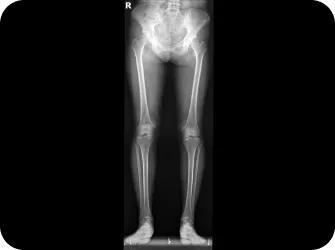

척추 엑스레이 검사

다리길이 엑스레이 검사